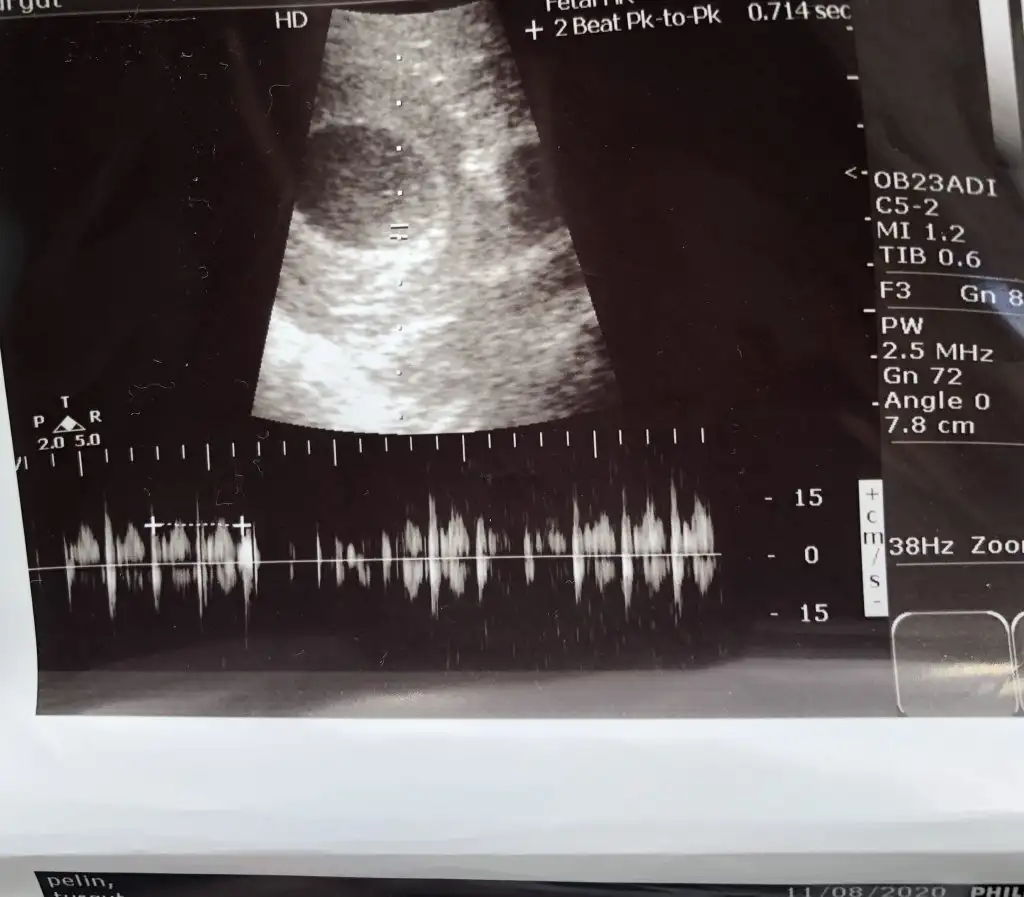

8+3 geç bu teori için yolk saç ne tarafta oluştuysa ona göre yorum yapmak lazım 6 veya 7 haftalık olmalıIkra meyra canım lütfen o güzel tahminlerinden bana da yapar mısın☺ 8+3 günlük karından usg

8+3 geç bu teori için yolk saç ne tarafta oluştuysa ona göre yorum yapmak lazım 6 veya 7 haftalık olmalı